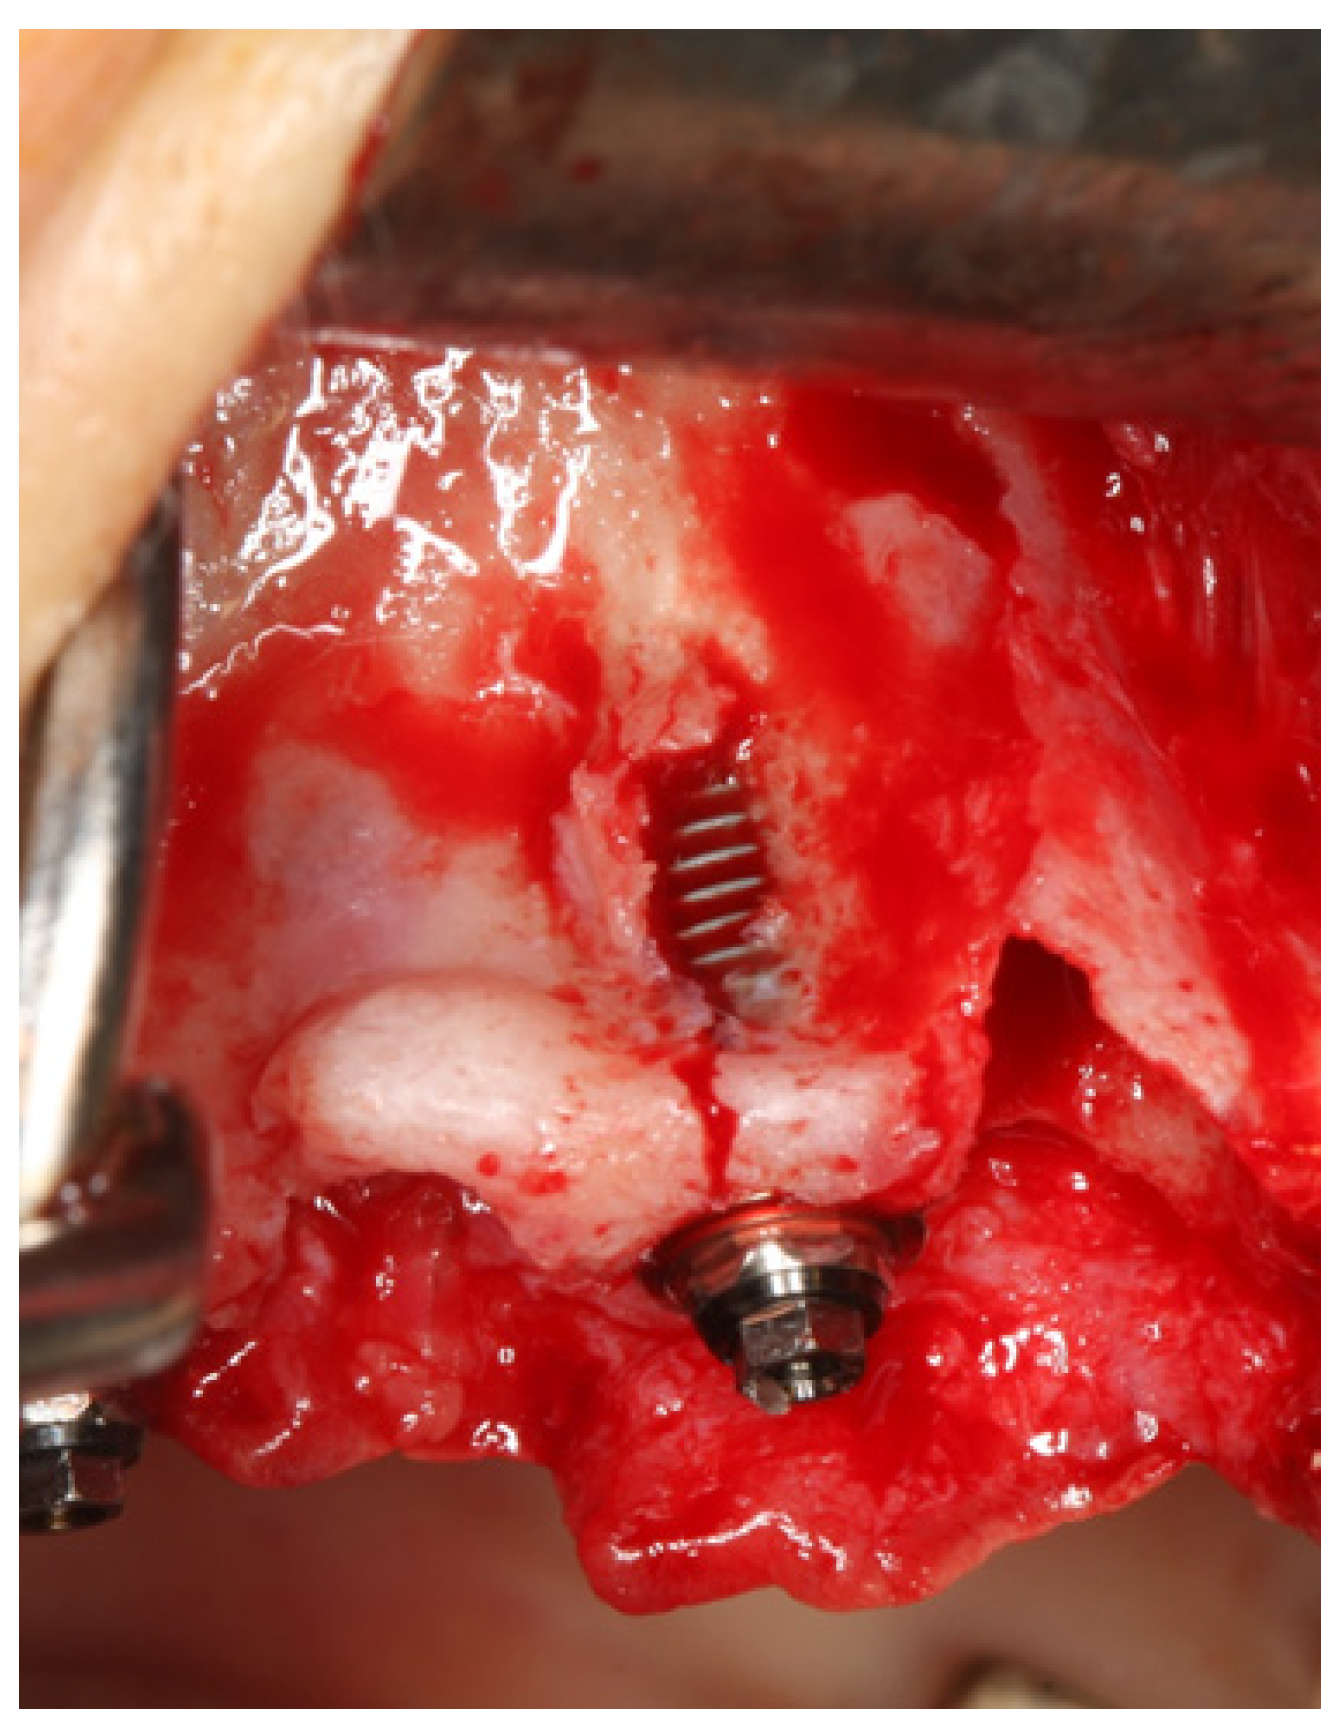

2. Materials and Methods